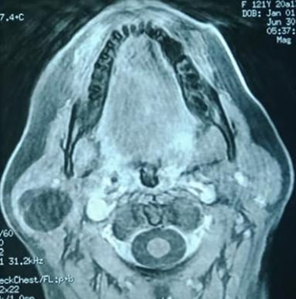

On magnetic

resonance imaging (MRI), a 31x26x30 mm oval-shaped lesion with well-defined

contours was identified in the inferior part of the superficial lobe of the

right parotid gland. It was partially extended to the

deep lobe. The lesion exhibited homogeneity and very high intensity on

T1-weighted images, high intensity on T2-weighted images, and low intensity on

diffusion-weighted images. The lesion was not enhanced after gadolinium

injection. This intensity pattern was identical to that of the fatty tissue (Figure 2).

Therefore,

the images suggested the diagnosis of parotid lipoma.

Figure 2. MRI images

show the fatty mass in the right parotid gland.